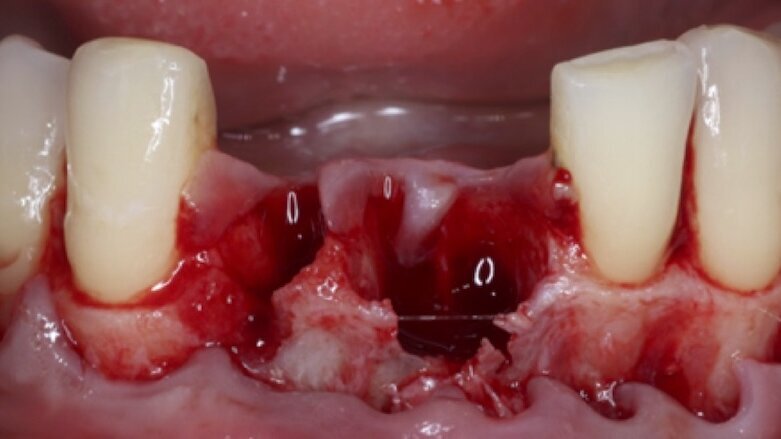

Figura 1. Regeneración ósea en maxilar severamente infectado, donde se utilizó terapia coadyuvante con vitamina D. (Foto: Iván Herrera Ustariz/Samia Isaac Tatis)

Los autores comentan que no hay estudios concluyentes sobre los efectos de los suplementos nutricionales de vitamina D en la oseointegración de los implantes dentales, pero que hay evidencia de que puede ser una terapia coadyuvante útil en pacientes con el metabolismo óseo alterado.

En nuestra práctica clínica, cada día se efectúan más procedimientos quirúrgicos de regeneración ósea y colocación de implantes dentales; algunos de estos pacientes presentan metabolismo óseo alterado, deficiencias o insuficiencias de vitamina D. Las publicaciones reportan la importancia de este compuesto en el proceso de la oseointegración; sin embargo, es fundamental realizar un estudio previo de laboratorio clínico para saber los niveles de suficiencia, deficiencia o insuficiencia de vitamina D, además de verificar los niveles de calcio sérico y paratohormona, y de esta manera poder ajustar las dosis requeridas de suplementos, previo a los procedimientos quirúrgicos de regeneración ósea e implantes dentales. Asimismo es adecuado orientar al paciente, con respecto a una buena alimentación y suplementación nutricional pre y post quirúrgica.

Revisando la literatura sobre el papel beneficioso de la vitamina D en la oseointegración, se puede observar que existe mucha controversia en el resultado de las investigaciones. Por consiguiente, lo que varios investigadores recomiendan es que se necesitan más estudios clínicos, con un diseño apropiado (estudios controlados aleatorios o prospectivos, en muestras más grandes, de pacientes con deficiencias graves) para investigar mejor este tema. Sin embargo, al estudiar la fisiología y el papel de la vitamina D sobre la homeostasis ósea, se sugiere que puede ser utilizada como terapia coadyuvante para el proceso de oseointegración en los implantes dentales, sobre todo en pacientes con metabolismo óseo alterado, para evitar la falla temprana, reportada por algunos autores.